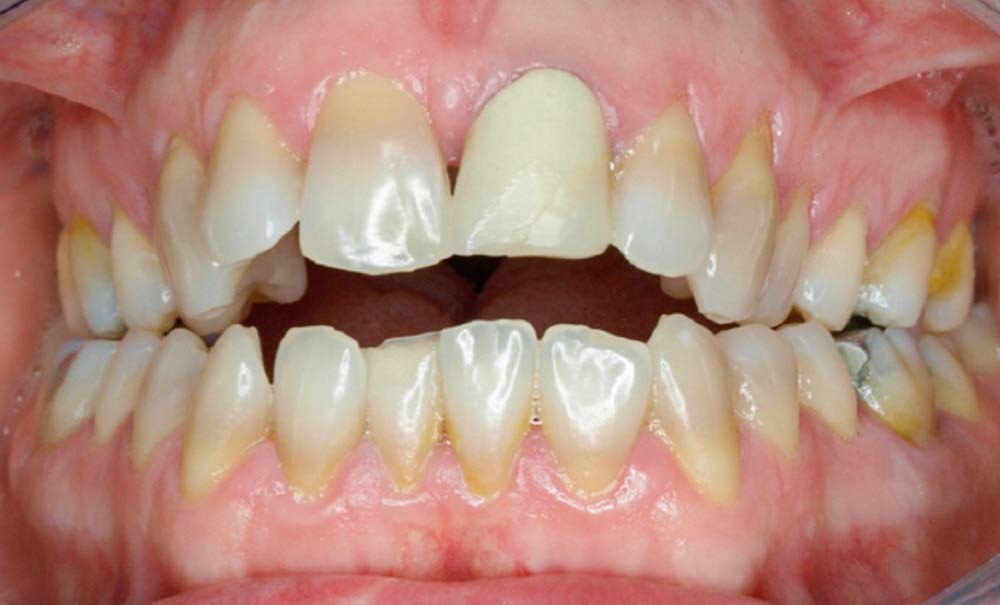

En 2008, la patiente, âgée de 34 ans, se présente pour le traitement de ses « dents mal placées, et de l’écart entre les dents du haut et du bas » (fig. 1). Elle a déjà bénéficié d’un traitement adolescent par plaque amovible maxillaire.

Au niveau exobuccal, la patiente présente un visage convexe avec un étage inférieur de la face augmenté et une absence de contact bilabial au repos traduisant un contexte dysfonctionnel. Le sourire est gingival et étroit.

L’analyse endobuccale et l’étude céphalométrique (fig. 2, tableau 1) confirment le diagnostic de classe II squelettique hyperdivergente avec une classe II molaire et canine bilatérale, associée à un encombrement, à une dysharmonie du sens transversal par endoalvéolie maxillaire, et une béance antérieure par infra-alvéolie incisive maxillaire dans un contexte dysfonctionnel de la musculature péri-labiale et mentonnière.